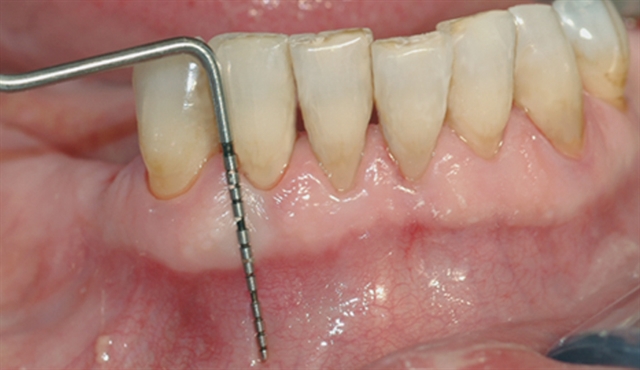

• Ei undersøking med lommeregistrering avdekkjer likevel eit omfattande beintap ved den eine

tanna.

• Instrumentet er her lagt utanpå tannkjøtet for å vise kor omfattande festetapet er.

• Beintapet vert bekrefta av eit røntgenbilete – skaden er så stor at tanna må fjernast.